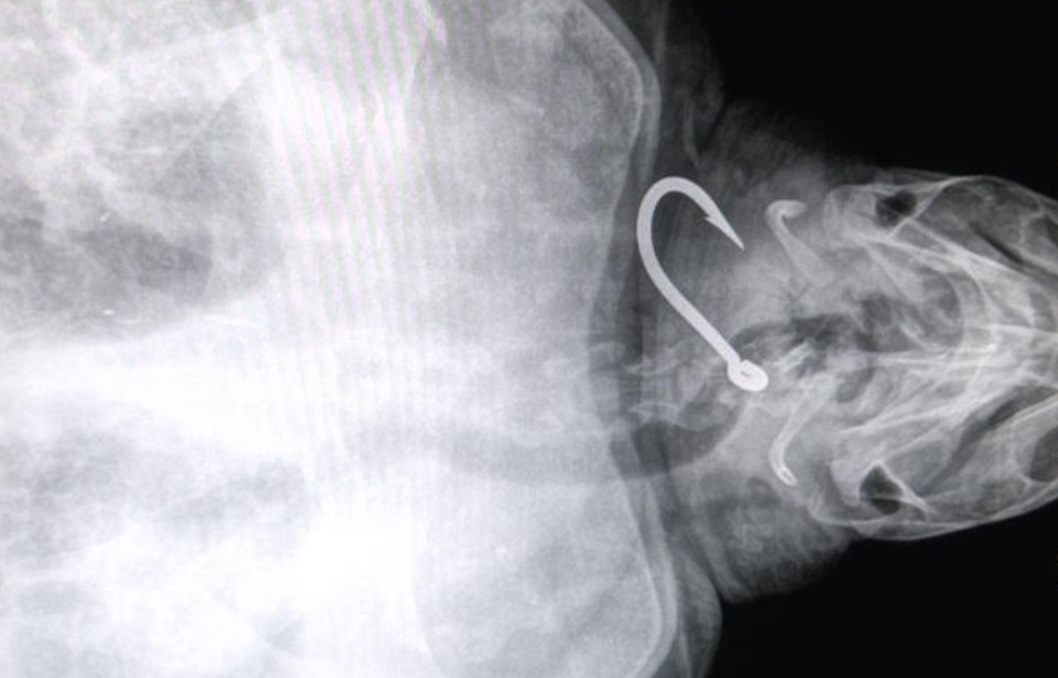

Des radios ont été réalisées lundi matin pour localiser les hameçons et déterminer le mode opératoire pour les retirer.

L’une des trois tortues avait avalé trois hameçons: un dans l’oesophage, un dans la partie distale de l’intestin, et un dans la trachée.

Cela montre que les hameçons se déplacent dans le corps de la tortue avec des conséquences parfois réduites, si ils suivent le transit intestinal - mais aussi plus graves lorsque les hameçons atteignent des organes sensibles, comme cela est le cas pour la trachée.

Un autre risque important lors de captures accidentelles, est l’enchevêtrement dans le fils de pêche qui reste attaché à l’hameçon. Cela peut provoquer un étranglement ou des amputations des nageoires. D’où l’importance d’intervenir le plus rapidement possible aprés que l’hameçon ai été avalés.